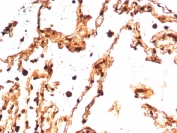

IHC staining of FFPE human lung tissue with S100A4 antibody (clone S100A4/7096). HIER: boil tissue sections in pH 9 10mM Tris with 1mM EDTA for 20 min and allow to cool before testing.